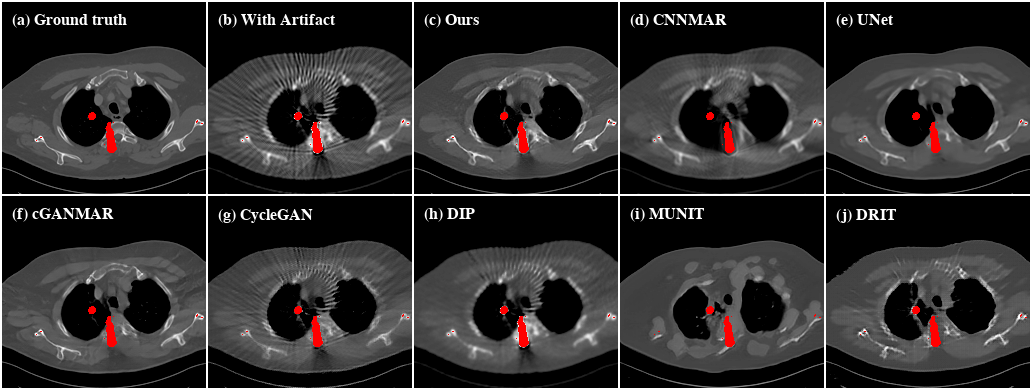

Refer to caption

Figure 10: Qualitative evaluation results of CL2.

Performance on clinical data.    Next, we investigate the performance of the proposed method on clinical data. Since there are no ground truths available for the clinical images, only qualitative comparisons are performed. The qualitative evaluation results of CL1 are shown in Figure 9. Here, all the supervised methods are trained with paired images that are synthesized from the artifact-free group of CL1. We can see that UNet and cGANMAR generalize poorly when applied to clinical images (Figure 9(d) and 9(e)). CNNMAR is more robust as it corrects the artifacts in the sinogram domain. However, such a sinogram domain correction also introduces secondary artifacts (Figure 9(c)). For the more challenging cross-modality artifact reduction task with CL2 (Figure 10), all the supervised methods fail. This is not totally unexpected as the supervised methods are trained using only CT images because of the lack of artifact-free CBCT images. Similar to the cases with SYN, the other unsupervised methods also show inferior performances when evaluated on both the CL1 and CL2 datasets. By contrast, our method consistently delivers high-quality artifact reduced results on clinical images.